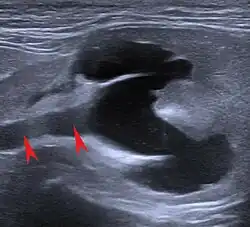

Die Ultraschalluntersuchung gestattet es, morphologische Veränderungen der Nieren detaillierter darzustellen. Neben Größen- und Formveränderungen lassen sich auch Nierenzysten, örtlich abgegrenzte (fokale) Organschäden, Wassersacknieren und Harnstauungen sowie Tumoren darstellen. Kaum abgegrenzte (diffuse) Organveränderungen gehen zwar mit Änderungen der Echogenität einher, sind aber nur selten definierten Erkrankungen zuzuordnen.[22] Mittels „Pulsed-Wave-Doppler“ lassen sich auch Durchblutungsstörungen nachweisen.[23] Häufig kommt es bei der chronischen Nierenerkrankung auch zu Verkalkungen (Nephrokalzinose), die sich ebenfalls sonografisch nachweisen lässt.[24]